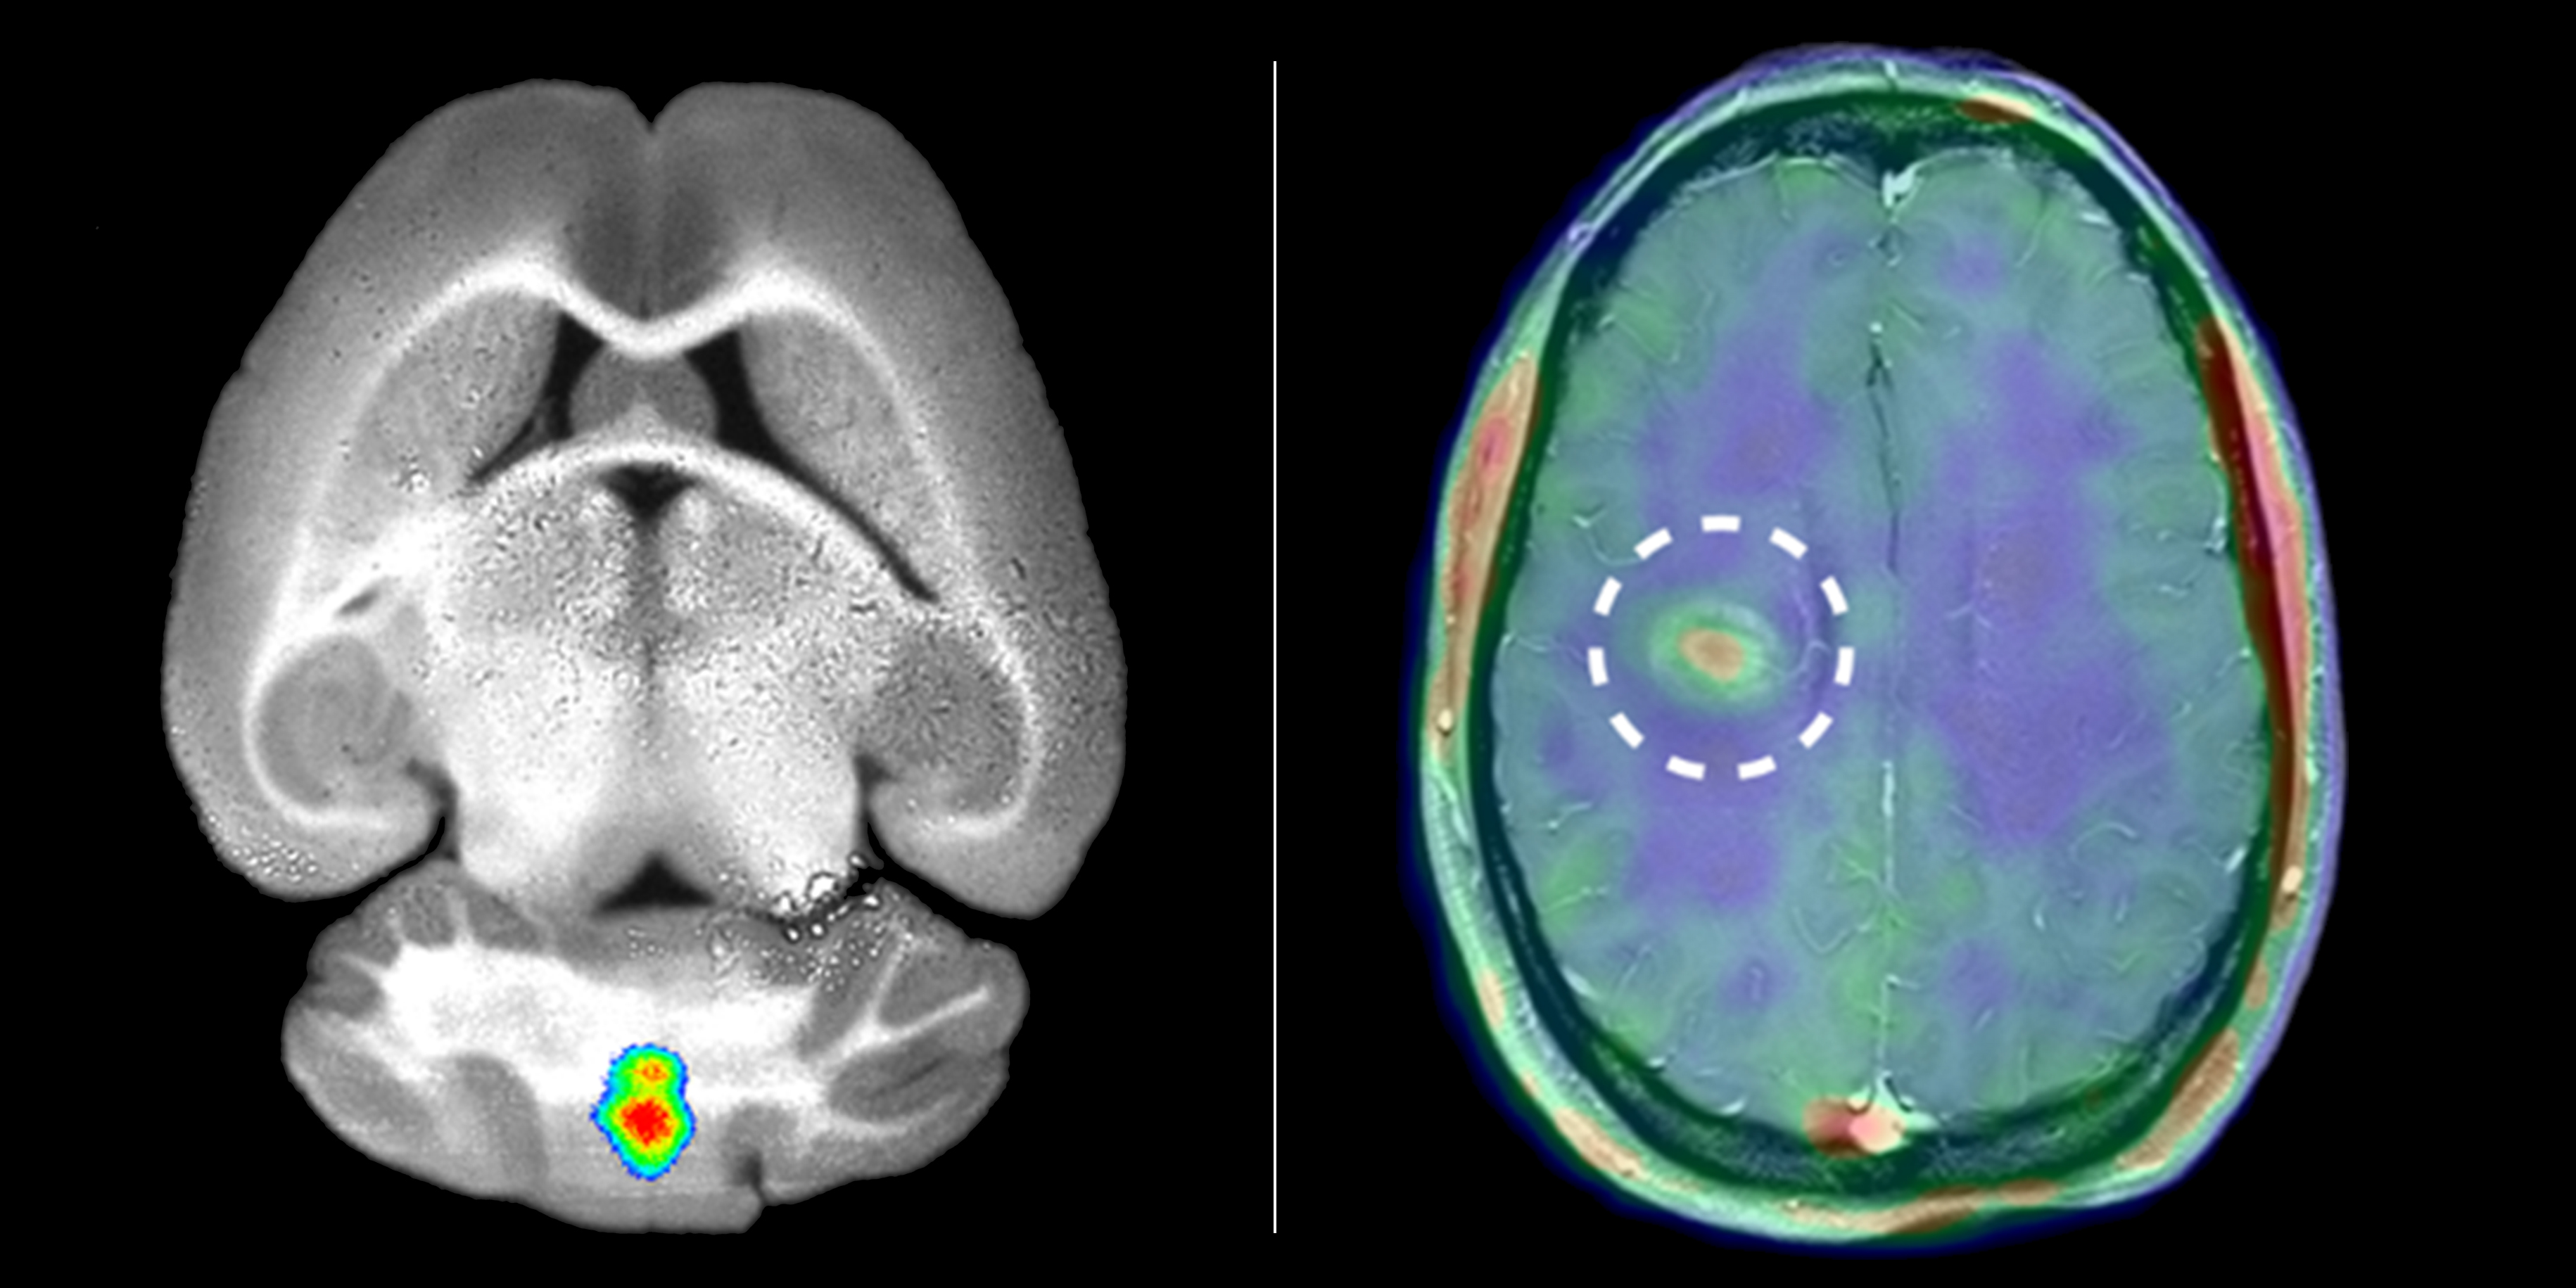

Researchers at the Cells-in-Motion Cluster of Excellence have visualized inflammation in the brain of mice (left) and of multiple sclerosis patients (right). To do so, they labelled specific enzymes (MMPs).<address>© Reprinted with permission from Gerwien and Hermann et al., Sci. Transl. Med. 8, 364ra152 (2016) 9 November 2016</address>

Researchers at the Cells-in-Motion Cluster of Excellence have visualized inflammation in the brain of mice (left) and of multiple sclerosis patients (right). To do so, they labelled specific enzymes (MMPs).

For the first time, CiM researchers have used certain enzymes – matrix metalloproteinases (MMPs) – to image inflammation in the brain that typically occurs during flares in MS patients. In a preliminary study, biologists and biochemists in a team headed by CiM Spokesperson Prof. Lydia Sorokin discovered that these enzymes play a pivotal role. They had investigated mice with a similar disease to MS and found that MMPs are essential for immune cell penetration of the blood-brain barrier and their migration into the brain, where they cause inflammation.

In order to label these enzymes in the brain and visualize them through specialized imaging techniques, a team of chemists and nuclear medicine specialists headed by one of CiM Coordinators, Prof. Michael Schäfers, developed a tracer – a chemical substance that tracks down the active enzymes in the body and binds to them. The chemists linked the MMP tracer with a fluorescent dye. The fluorescence light signals from such a tracer can be measured using optical imaging techniques. Via the tracer signal the researchers were able to localize and measure the activity of the enzymes, initially in mice. "We found that our observations of MMP activity provided precise information on where immune cells penetrate the blood-brain barrier and where inflammation occurs in the brain," says Dr. Hanna Gerwien, a molecular biologist.

The researchers have now succeeded in transferring the method to humans. However, it was not possible to use the fluorescent tracer because its light signal would not penetrate the skull of a patient. The researchers therefore modified the tracer, adding a radioactive signal transmitter instead of a fluorescent dye. The radiation it emits can be measured and made visible using a special method, positron emission tomography (PET). Nuclear medicine specialists and neurologists at the Cluster of Excellence in Münster (who also work at Münster University Hospital) have now carried out the first case studies on MS patients. The result was that in patients with acute attacks of MS the tracer accumulated clearly in defined areas, even before any damage to the blood-brain barrier could be measured using the traditional method, magnetic resonance imaging.